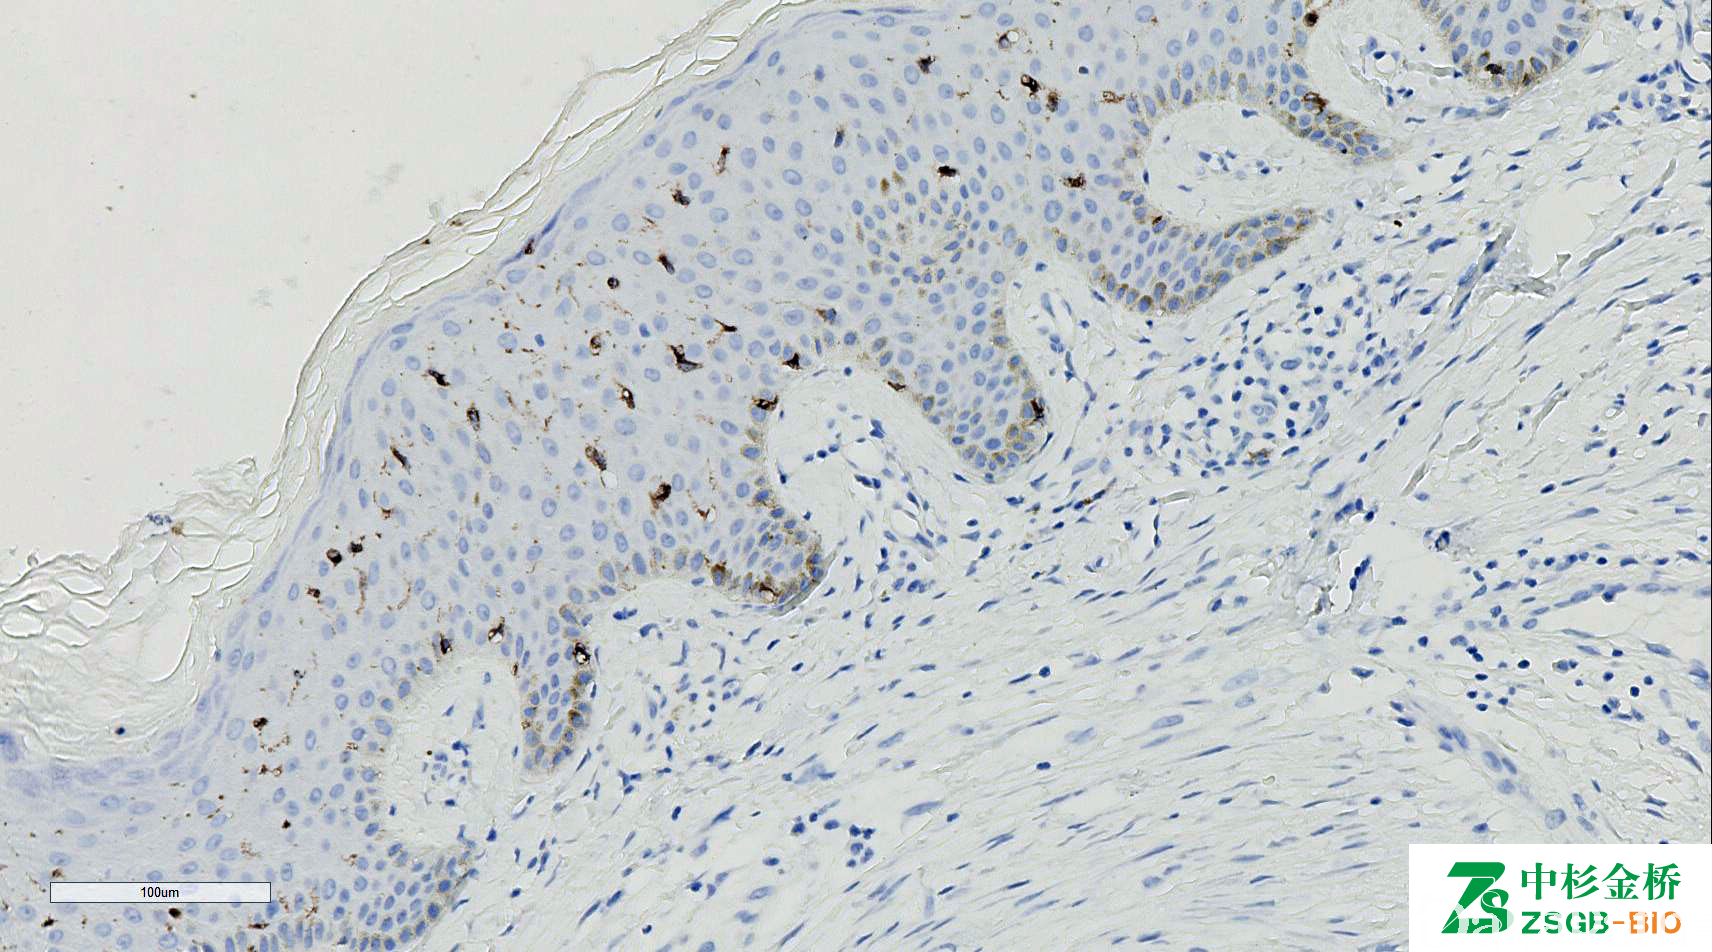

LANGERIN

由 Langerhans 细胞产生,是具有甘露糖结合特异性的 II 型跨膜 C 型凝集素,介导 Birbeck 颗粒形成。

信号定位: 胞膜